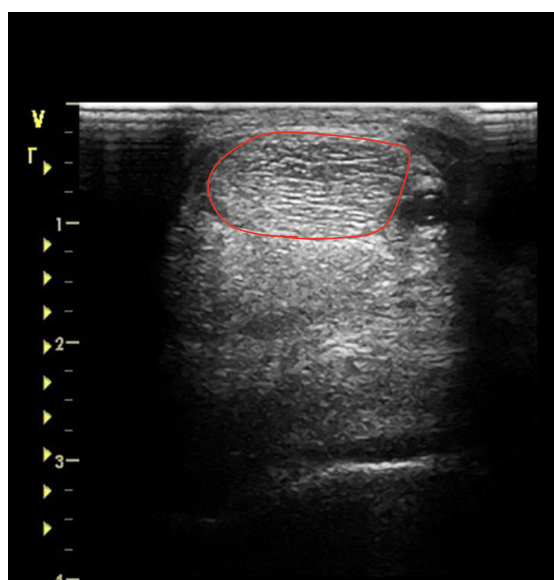

what is the red circling?

suspensory ligament at the mid MC 3